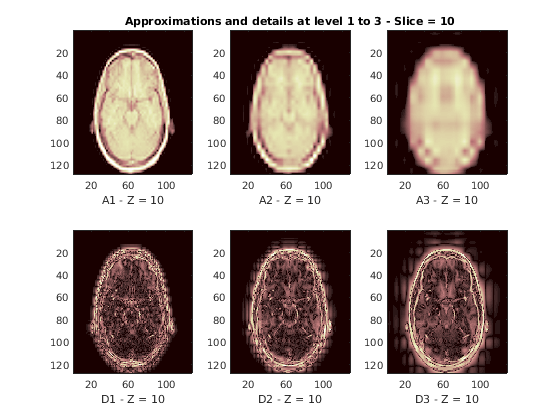

Восстановленные приближения и детали вдоль Z-ориентации отображены ниже.

nbIMG = 6; idxImages_New = [1 7 10 16 19 25]; for ik = 1:nbIMG j = idxImages_New(ik); figure('DefaultAxesXTick',[],'DefaultAxesYTick',[],... 'DefaultAxesFontSize',8,'Color','w') colormap(map) for k = 1:n labstr = [int2str(k) ' - Z = ' int2str(j)]; subplot(2,n,k) image(A{k}(:,:,j)) xlabel(['A' labstr]) if k==2 title(['Approximations and details at level 1 to 3 - Slice = ' num2str(j)]) end subplot(2,n,k+n) imagesc(abs(D{k}(:,:,j))) xlabel(['D' labstr]) end end